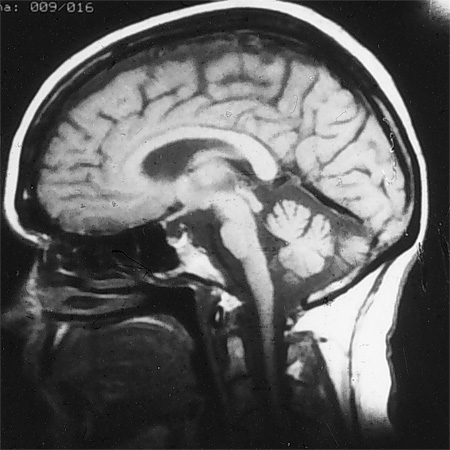

Ressonância nuclear magnética (RNM) do cérebro mostrando atrofia cerebelar e do tronco encefálico na SCA 1

Do acervo de Dr. S. H. Subramony; usado com permissão